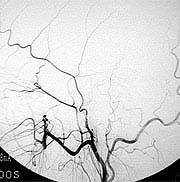

すでに詰まってしまっている患者さんに対しては症状が軽い場合であれば、頭蓋内血管と頭蓋外血管とのバイパス手術を行い、症状の悪化を予防しています(図11,図12,図13)。